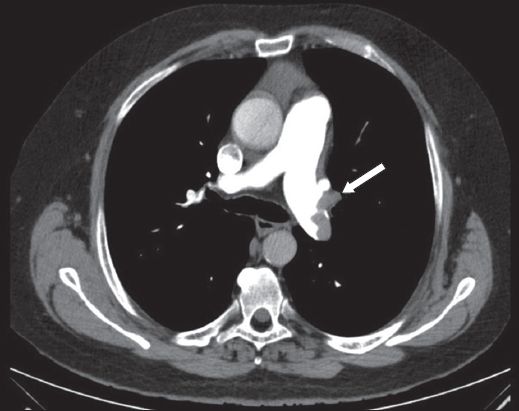

Initial blood investigations revealed an elevated D-dimer level of more than 4.0 μg/L and an elevated troponin I level of 0.118 μg/L. In view of the suggestive history, risk factors and ECG changes, a CT-PA was performed, which showed the presence of a saddle embolus and emboli in the bilateral pulmonary trunks (

Fig. 4

Case 2: CT image shows a filling defect (arrow) in the left main pulmonary trunk of the pulmonary artery.